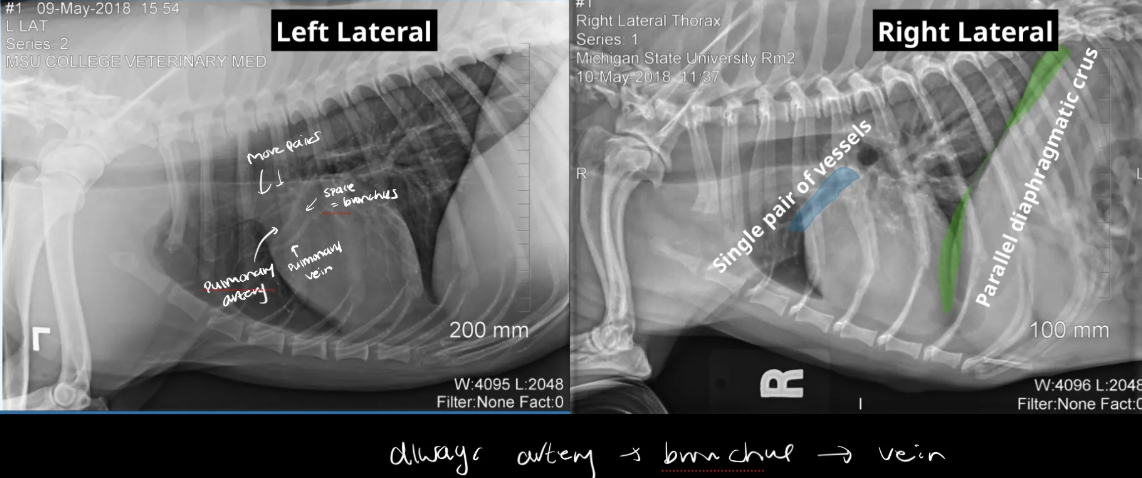

how to distinguish btw right lateral and left lateral?

right lateral: parallel disphragmantic crus + only one cranial pulmonary vessels visible

left lateral: diaphragmatic crus creates y-shape + two pairs of vessels

on lateral views,

artery - cranial or caudal

vein - cranial or caudal

A

artery - cranial

vein - caudal

(bronchus -black space btw these two)